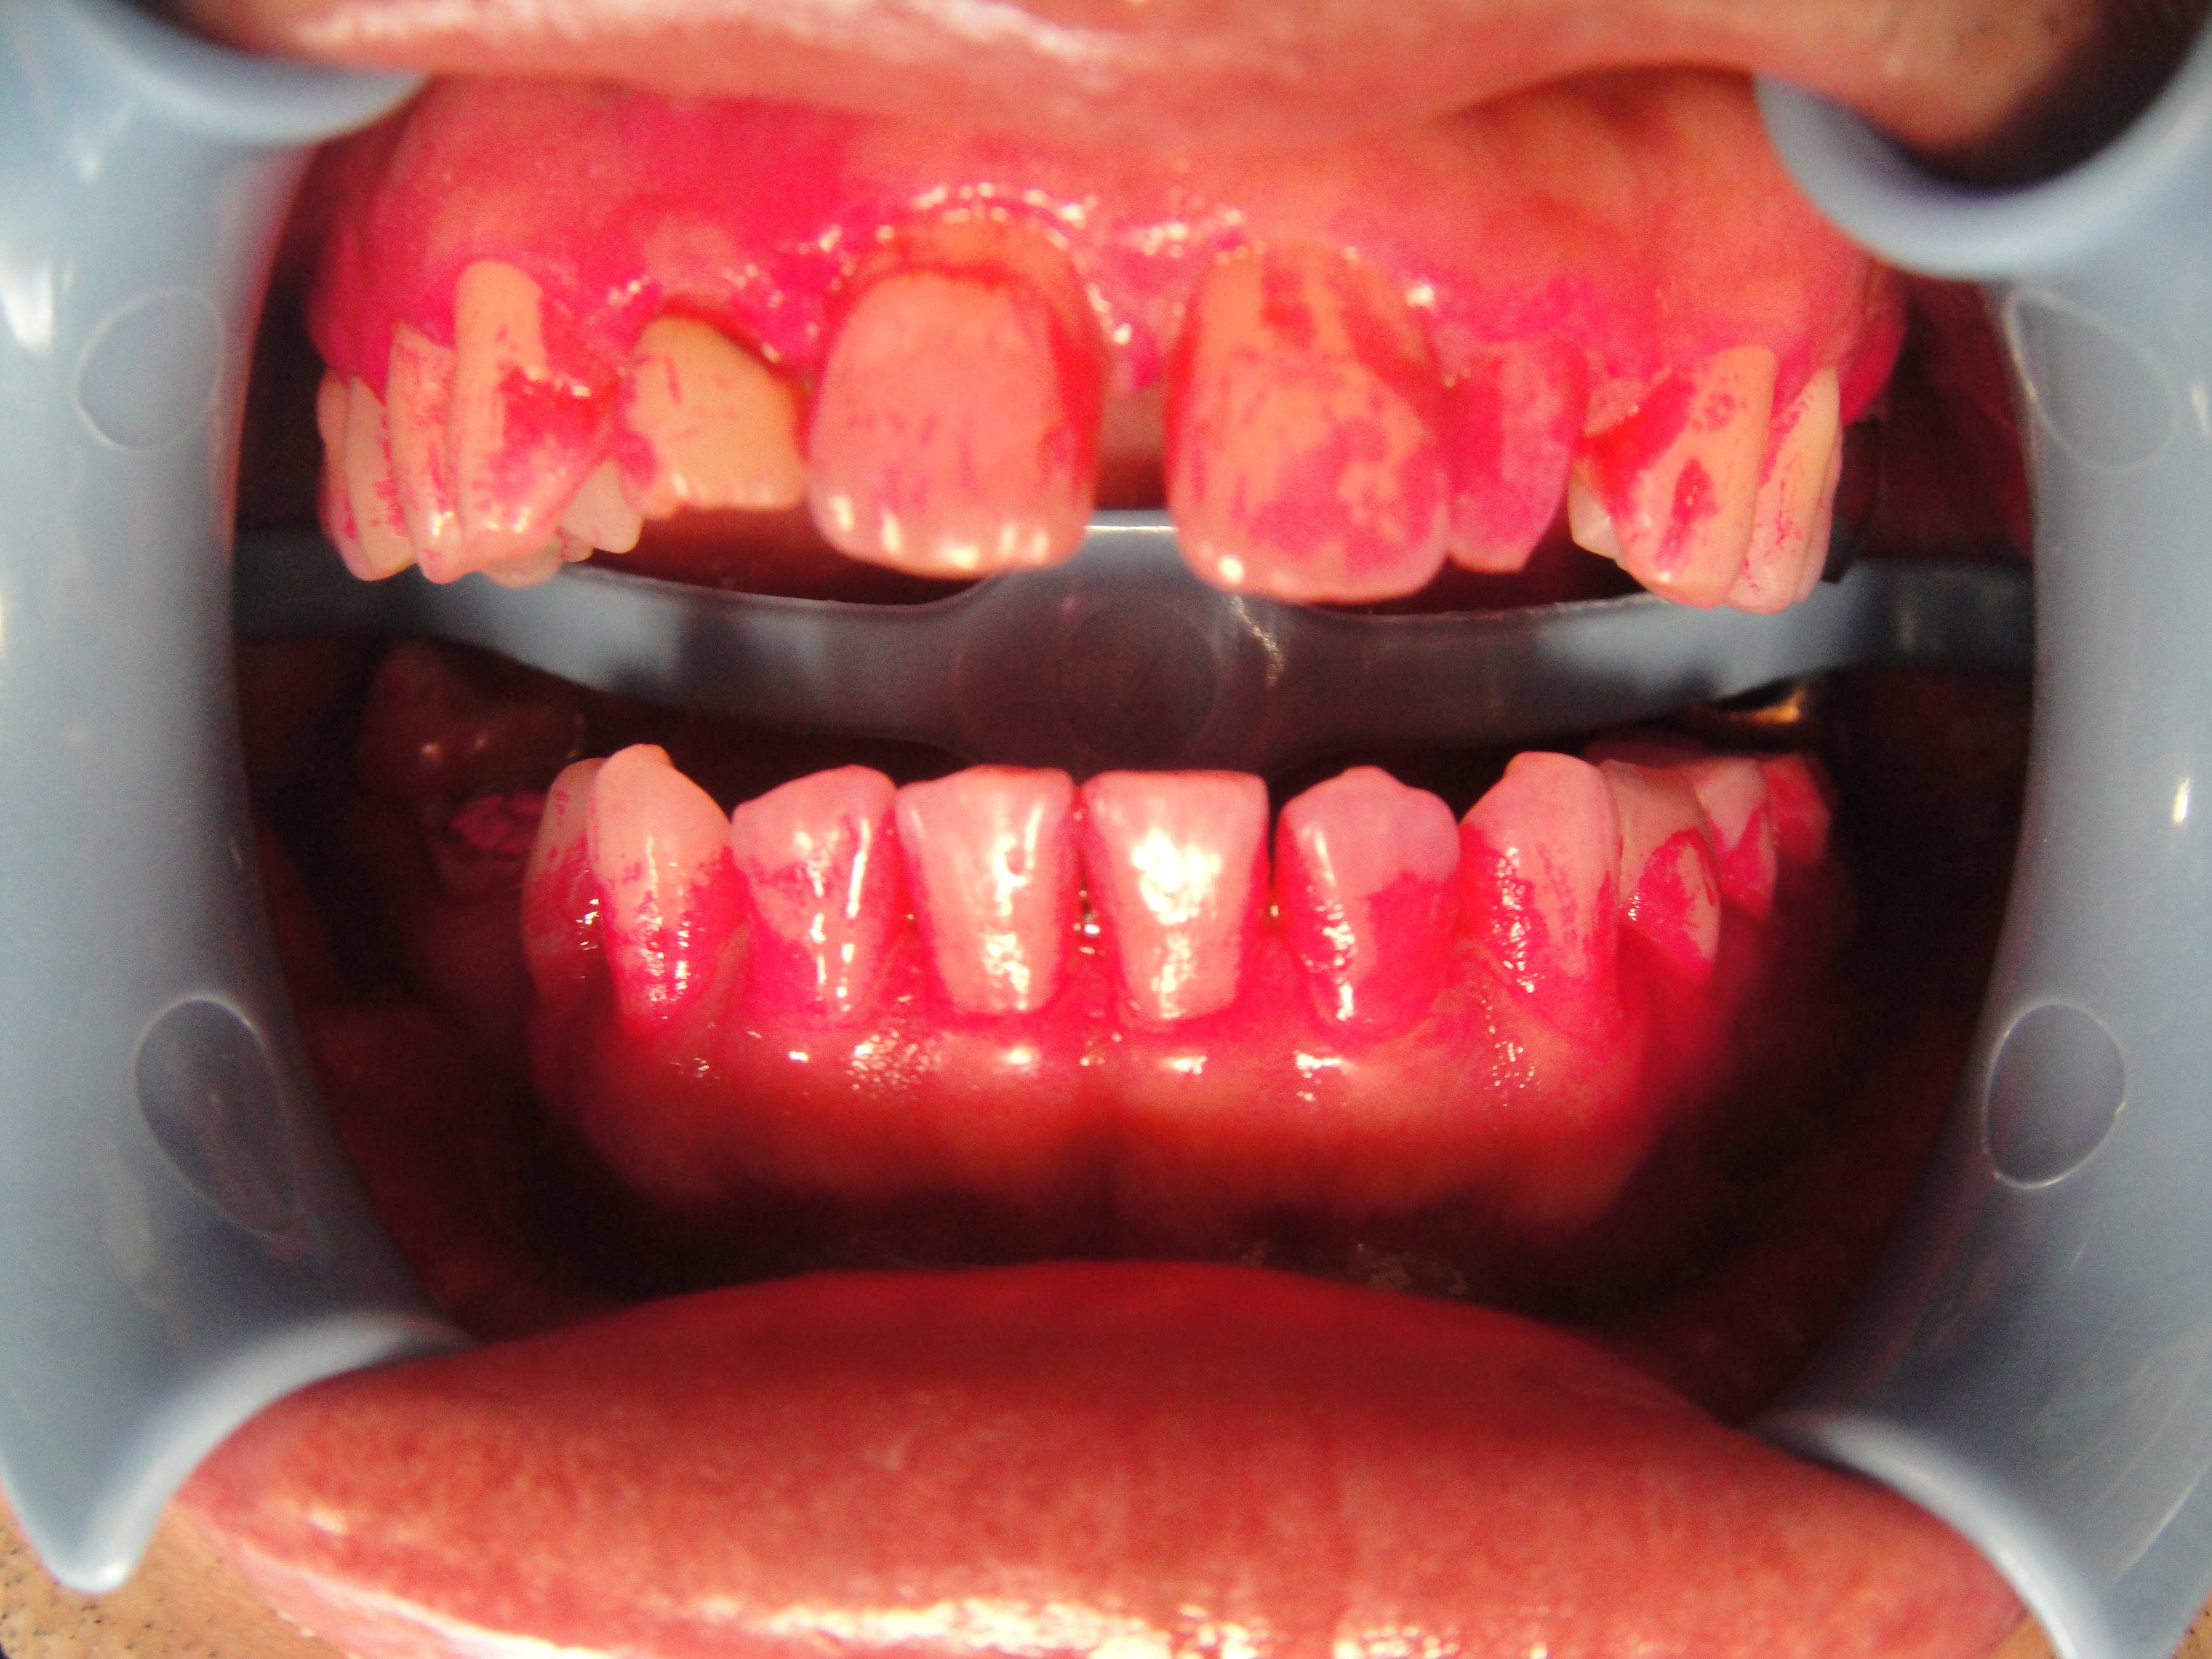

~33歳男性、来院前に歯磨きしてきたのに歯垢染だし液で染め出してみるとこんなに汚れが残っています。

赤くなっているところが、磨き残した歯垢。歯周病予防にも虫歯予防にも、歯垢除去はとっても大切。

歯垢は食べかすではありません。細菌の塊なんですよ~